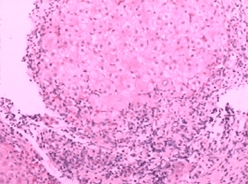

2.肠黏膜及黏膜下血管扩张和黏膜固有层水肿增厚为PHC特征性组织学表现。光镜下可见结肠黏膜水肿、淤血、大量毛细血管扩张,并偶见动-静脉短路,可伴有黏膜组织轻微炎症,少数肠黏膜固有层淋巴细胞轻度增生,黏膜固有层可见轻度淋巴细胞和浆细胞浸润;黏膜上皮细胞脱落坏死,形成糜烂而致出血;部分病例黏膜下层或肌间神经丛可见水肿及神经细胞变性。电镜下可见毛细血管内皮和黏膜上皮细胞超微结构改变。